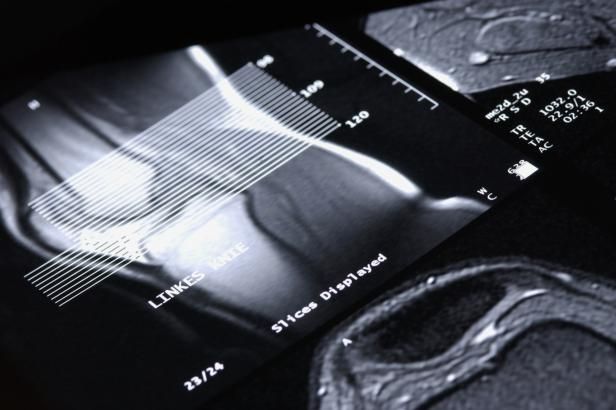

obrázek: Sportovci mohou jásat. Nová náhrada menisku umožňuje plnou zátěž

Sportovci mohou jásat. Nová náhrada menisku umožňuje plnou zátěž